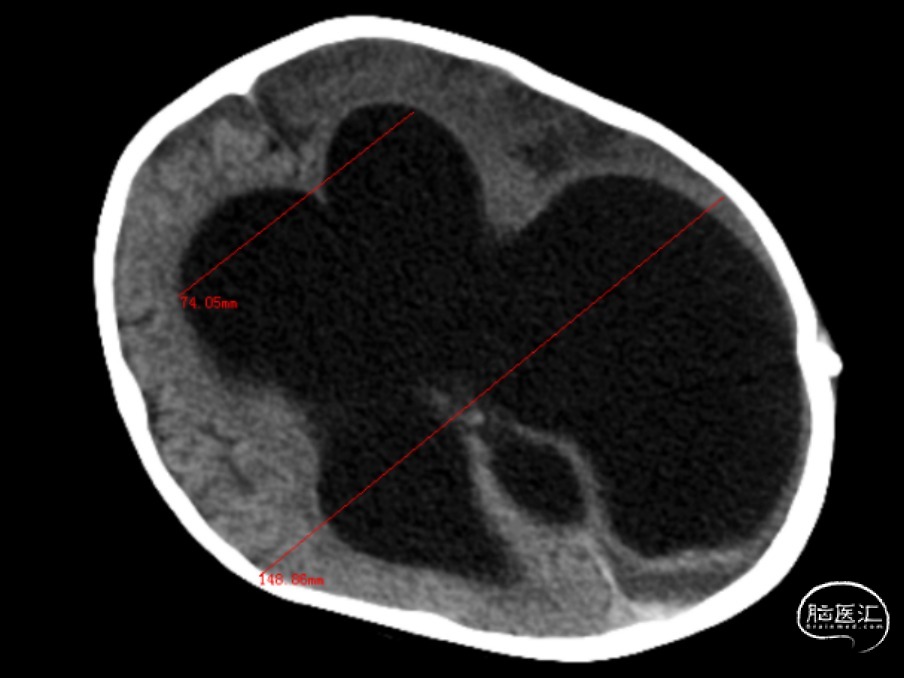

术前CT

Evans index(EI)≈0.55

重度脑积水,透明隔腔明显增宽,双侧脑室、三脑室、脚间池明显扩张、积水,周围脑实质受压,左侧大脑半球脑梗死。